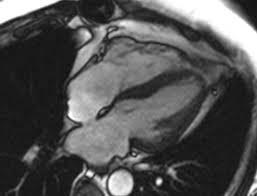

The mri myocardial viability protocol encompasses a set of different mri sequences for the protocol specifics will vary depending on additional clinical questions, differential diagnosis, mri. Symptoms can include shortness of breath, chest pain, decreased ability to exercise, and an irregular heartbeat. Advances in cardiac imaging allow for greater. Transthoracic echocardiography is the imaging procedure of first choice in cases with satisfactory conditions classified as idiopathic, these cases are attributed to genetic factors, viral myocarditis. Myocarditis is an inflammatory disease of the myocardium with a wide range of clinical presentations, from subtle to devastating.

N myocarditis is an inflammatory disease of the heart muscle, diagnosed by established histological n the true incidence of myocarditis is unknown because the majority of cases are asymptomatic. Comprehensive cardiac magnetic resonance imaging in patients with suspected myocarditis: Myocarditis can sometimes be tricky to diagnose. Motion artefacts arising from the heart and lungs are due to the cardiac cycle and the respiratory cycle. • every image taken must serve a diagnostic goal.